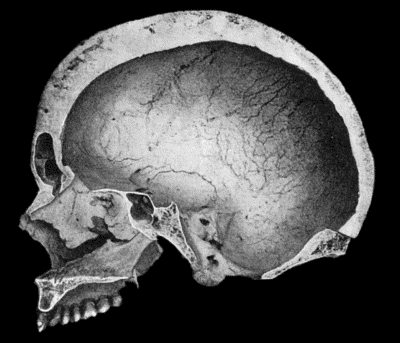

130.Syphilitic Disease of Skull 463

134.Changes in the Skull resulting from Ostitis Deformans 474

135.Cadaver, illustrating the alterations in the Lower Limbs resulting from Ostitis Deformans 475